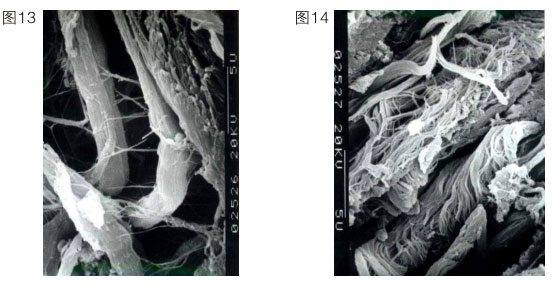

上述內(nèi)容說明再生復原重要的是要恢復其皮膚正常的生理功能。正常人的皮膚衰老了,意味著他皮膚的很多功能缺失了或退化了。因此我們的皮膚再生必須控制細胞,讓細胞強壯,恢復正常生理功能。我們在實踐中就啟動了角蛋白十九型干細胞,當然也可以啟動角蛋白十九型以下的細胞。我們首先把表皮基底層細胞啟動起來,使它可以增加生命活力,重建,同時成纖維細胞也更新。一個90歲的老人,基底細胞只有5%是有功能的。人一旦衰老了,細胞就難以再生到足夠的數(shù)量,所以一定要保證再生物質(zhì)的量,確保細胞的功能。一般來說,成纖維細胞的功能,隨著年齡的增長會代謝低下,這個低下指的是產(chǎn)生纖維的速度減慢、產(chǎn)生的量減少,產(chǎn)生的膠原纖維不成束。一個正常細胞產(chǎn)生的纖維如左圖所示(圖13),一個衰老的細胞產(chǎn)生的纖維如右圖所示。(圖14)這個衰老的細胞產(chǎn)生的絲是雜亂無章的,沒有彈力,又散又少。人老了,在細胞里產(chǎn)生的原纖維

就雜亂無章,成纖維細胞吐出來的纖維也就不成束了。所以他的皮膚組織里面就是空洞的,皮膚就不緊致。我們再生物質(zhì)的功能就是要把這種細胞不正常的功能糾正過來。我們要增加細胞的活性。皮膚真皮的豐滿程度,是靠成纖維細胞活力的增強來實現(xiàn)的。在活力沒有增強之前先把產(chǎn)生的纖維成束,一邊成束,一邊更新。這樣就出現(xiàn)一個保持年輕復原狀態(tài)。這個皮膚再生復原的時間問題涉及代謝時間問題。表皮的創(chuàng)傷性修復速度快,一般7天修復完成。一個正常人的表皮生理代謝,則是7天一層,基底層到角質(zhì)層是30層細胞,三七二百一十天。一個完全曬黑的人經(jīng)過210天可以復原回原來的顏色。皮膚表面的黃褐斑、老年斑我們都可以解決,但不是用激光、光子消掉就可以了,這樣還會再長,因為是細胞的異常屬性沒變。我們是用再生改變這個細胞的異常屬性,激活二次生命細胞,使皮膚再生復原。